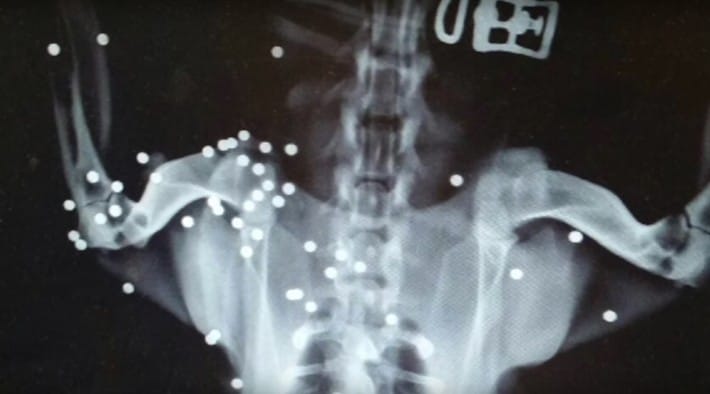

Sans hésiter, elle l'a immédiatement emmené chez un vétérinaire, qui a passé un aimant sur la peau de la chienne. Le test a montré qu'elle avait de nombreux fragments métalliques sous la peau.Pour confirmer leurs soupçons, ils ont ensuite fait passer une radio à Honeybee, et le résultat les a choqués. Son corps était criblé de plombs de fusil. Le vétérinaire témoigne de sa stupéfaction.

Personne ne s'attentait à quelque chose d'aussi grave. La quantité de plomb qu'elle avait à l'intérieur de son corps était ahurissante. Quelqu'un lui a probablement tiré dessus volontairement.

La plupart des plombs étaient concentrés sur l'arrière de son corps, ce qui indique qu'on lui a probablement tiré dessus alors qu'elle tentait de s'enfuir.